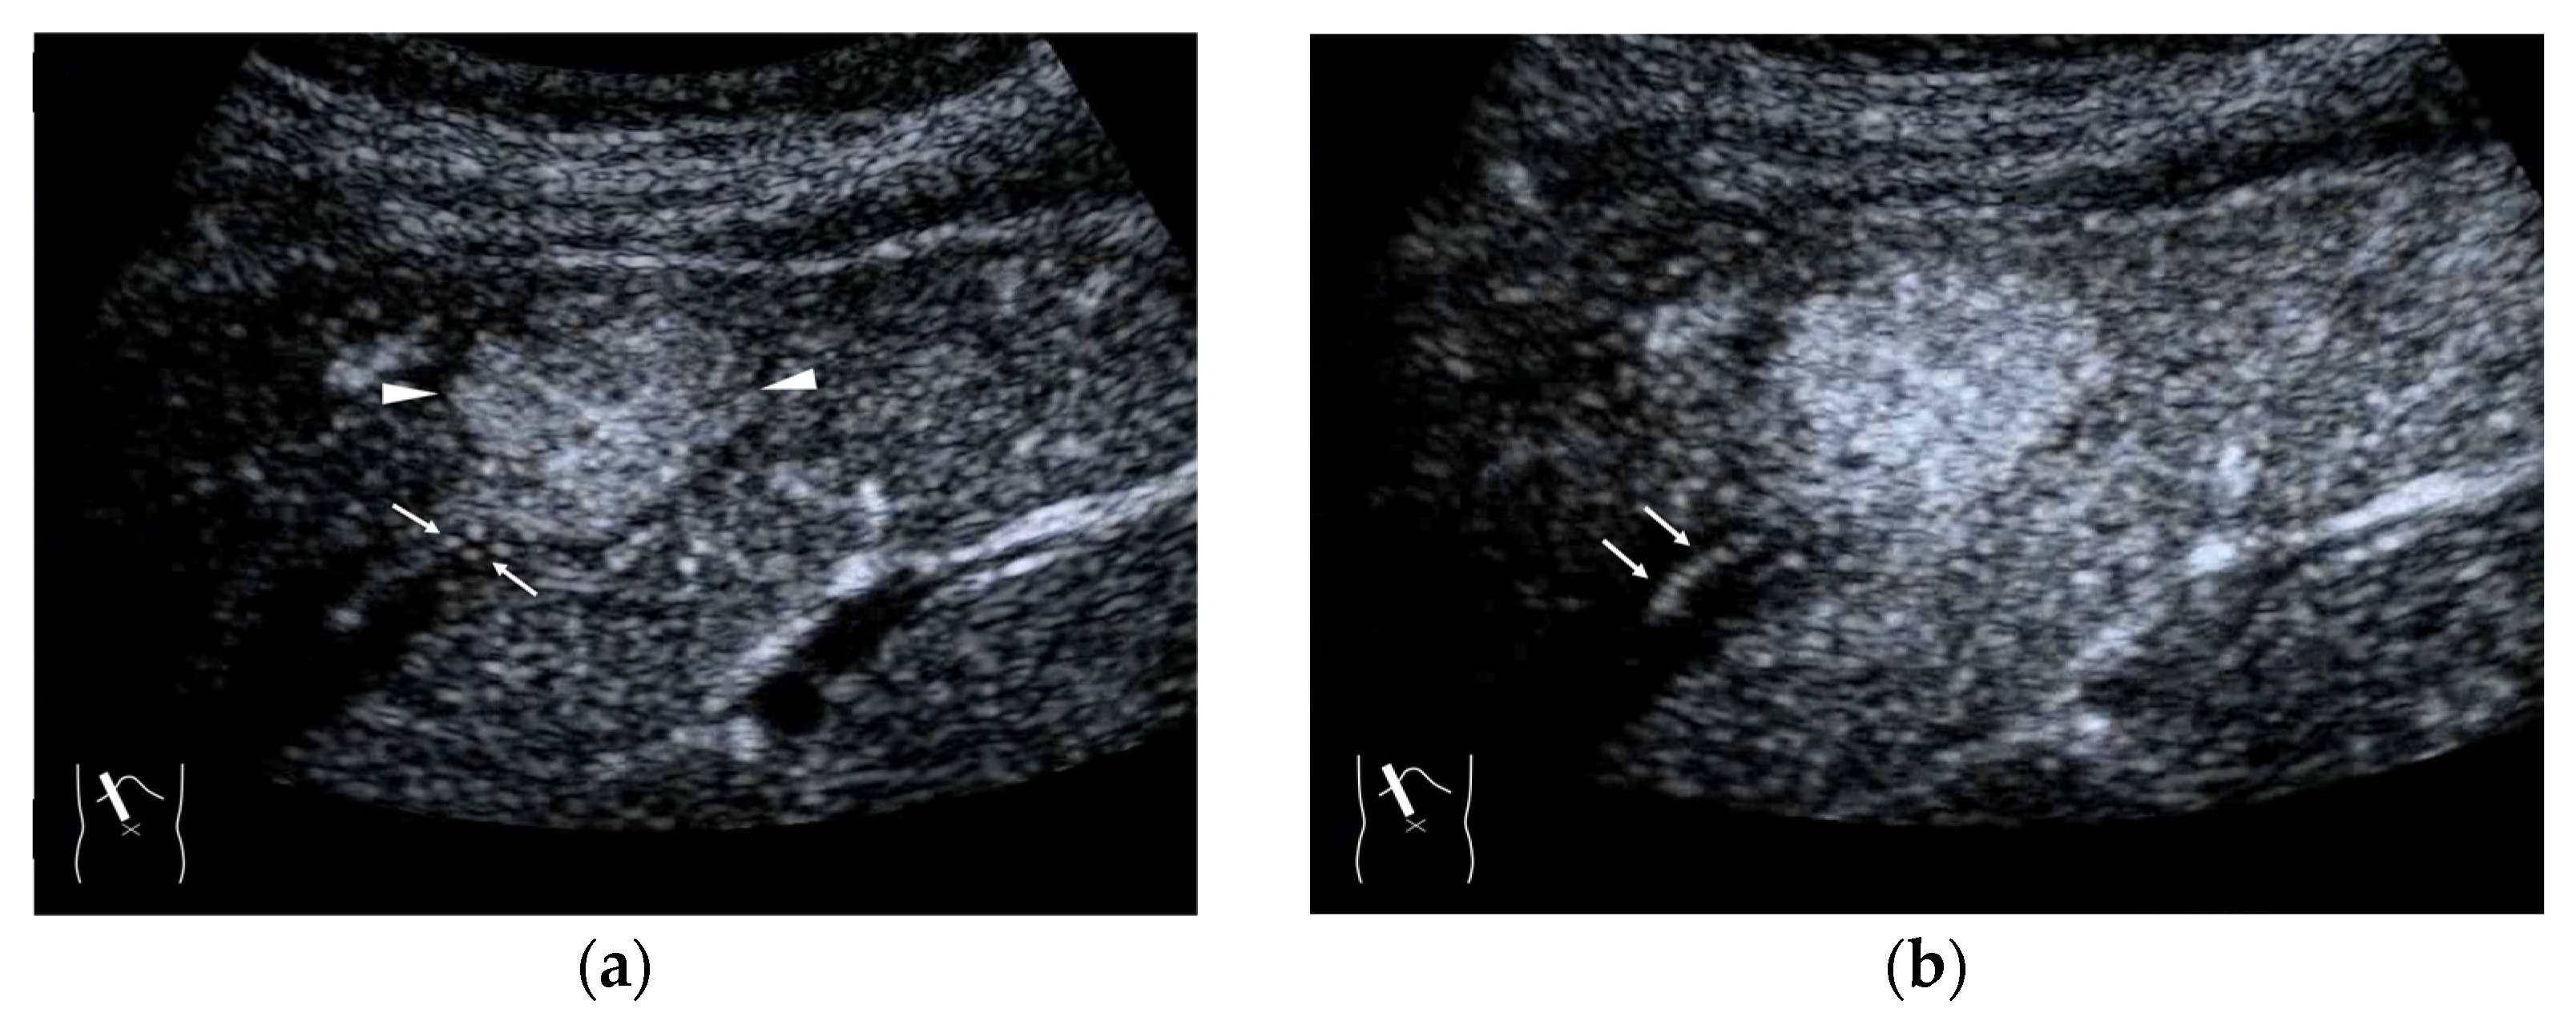

4.4. Hemodynamic Abnormalities in Liver Abscess

4.5. Hemodynamic Abnormalities in Liver Necrosis

4.6. Hemodynamic Abnormalities in Acute Cholecystitis